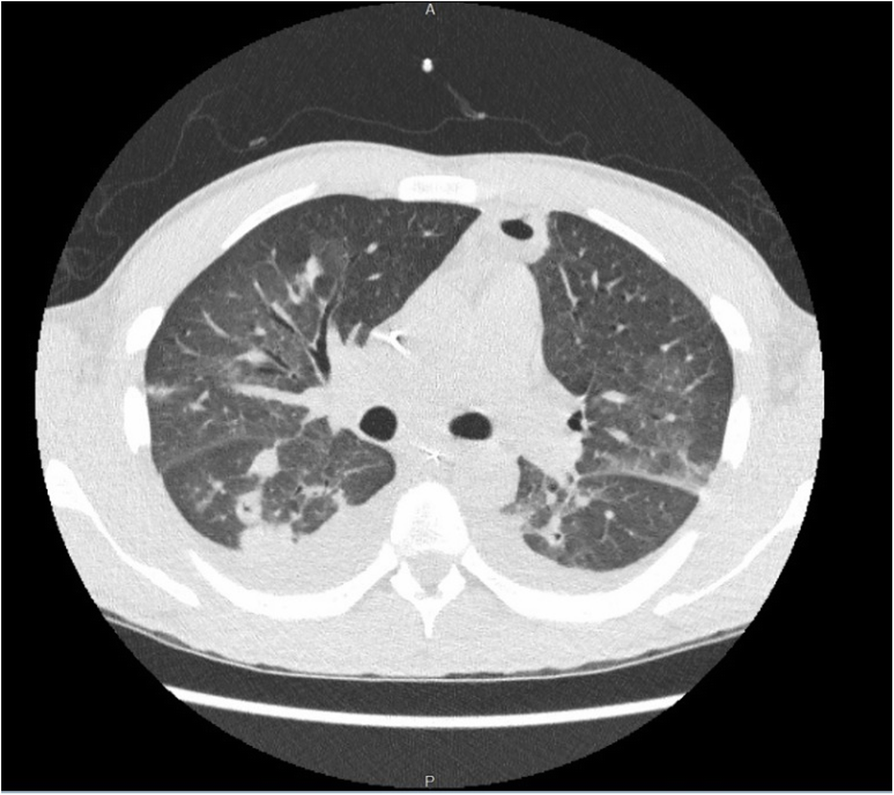

Fig. 2

Diffuse interstitial thickening with cavitary changes in multiple bilateral lung nodules with thick walls. Consolidative opacities with some lucent areas which may suggest cavitary changes